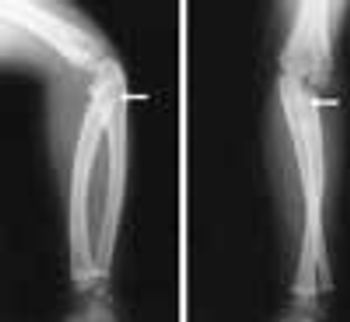

A 16-year-old African American boy complained of exertional pain below his left knee that severely limited his ability to participate in sports. The patient had had bilateral bowed legs until his early school years, when the right knee straightened. For the past year, exertional pain had been present below the left knee in the epiphyseal area.